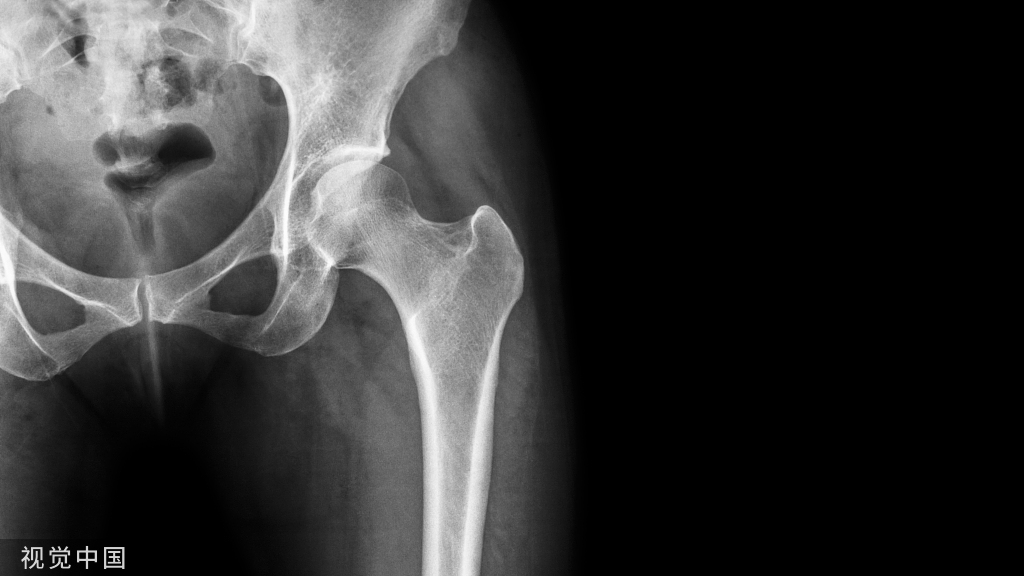

尺骨鹰嘴骨折发生率约占全身骨折的1.17%,是一种关节内损伤,因此常伴随关节内积血和组织液渗出。患者表现为肘关节疼痛、肿胀及活动受限,同时骨折端可触及凹陷。该骨折最重要的体征为抗重力伸肘丧失,表明伸肌装置连续性中断。该体征对治疗方案至关重要,在临床上往往需结合X线来明确诊断。